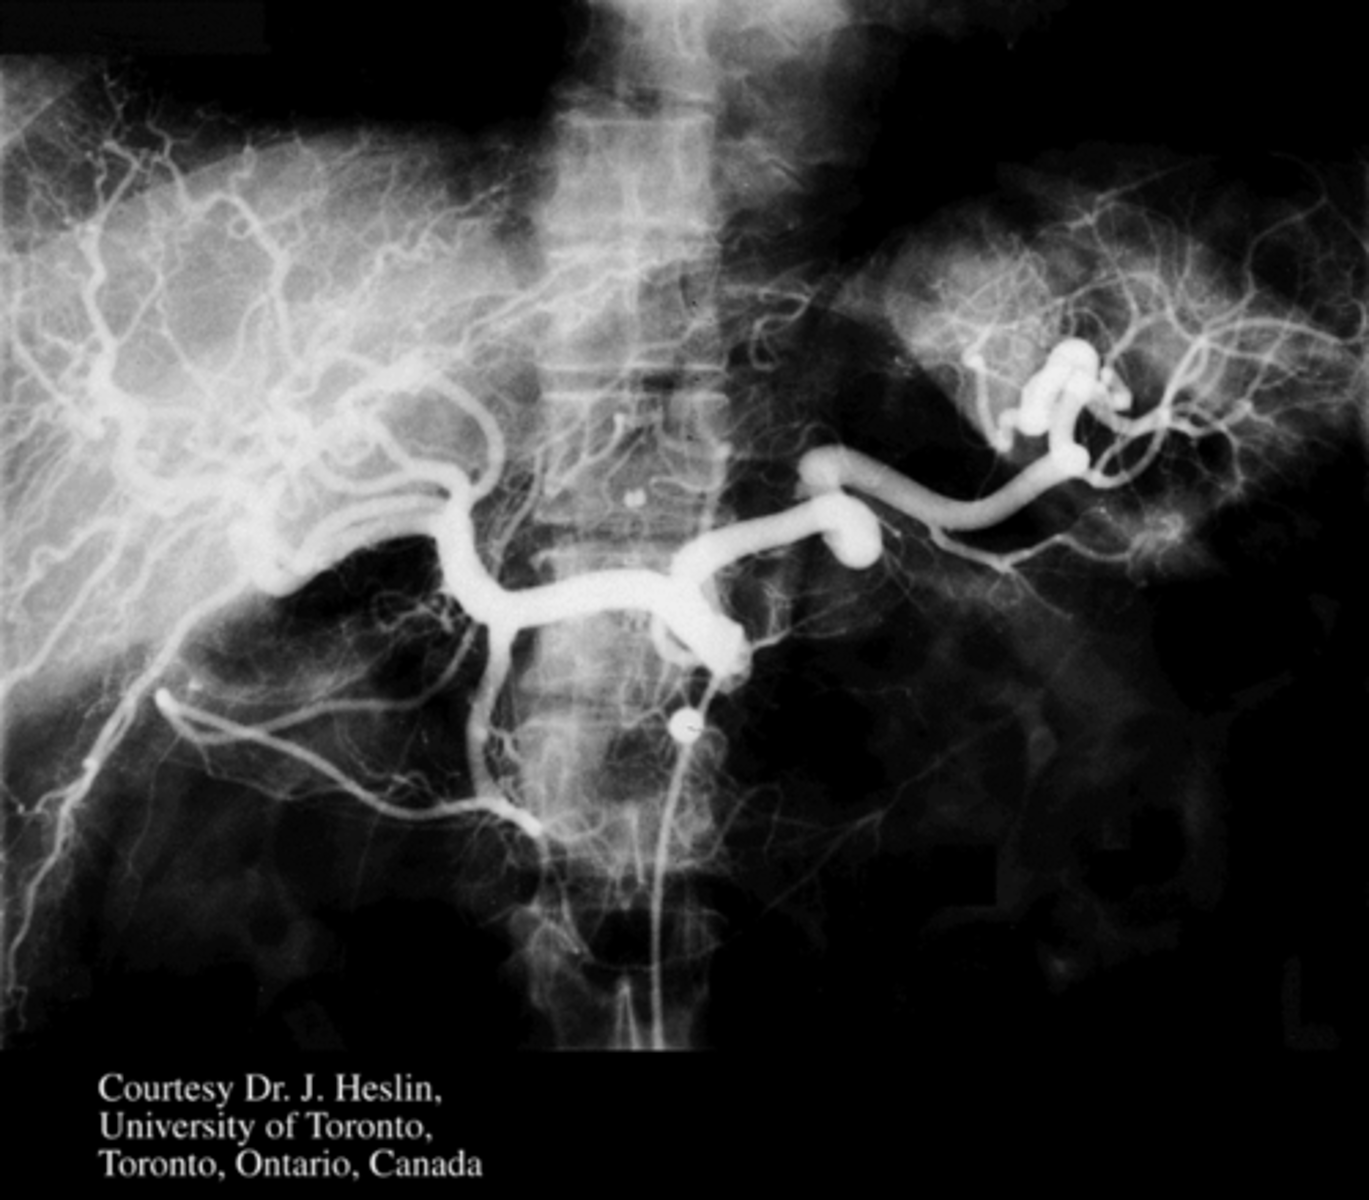

Identify pertinent anatomy in the following radiograph

SMA

<p>SMA</p>